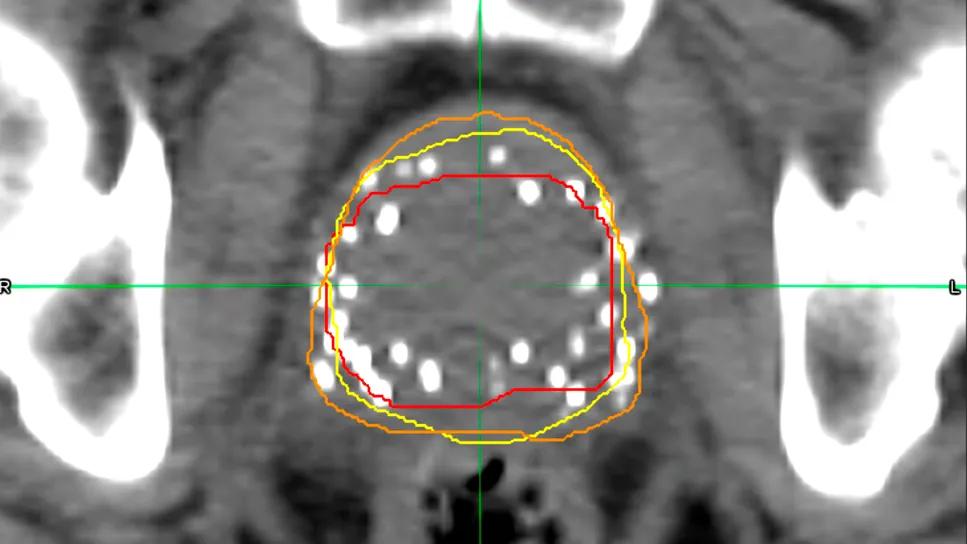

CT scan after prostate brachytherapy

Although there are sizeable variations between AI- and human-generated contouring of CT scans after prostate brachytherapy, a recent study finds no notable differences in patient outcomes. The study data was presented at the 2025 annual meeting of the American Society for Radiation Oncology (ASTRO).

Auto-contouring software is a relatively new innovation that offers a potential alternative to time-consuming manual contouring of CT scans by physicians for post-implant quality assurance. However, these AI-generated contours don’t always match those drawn by physicians. Now a small study by Cleveland Clinic researchers shows that — despite discrepancies on the screen — patient outcomes between the two approaches are the same.

For the study, researchers compared two different auto-contouring systems against standard physician-drawn contours for 100 patients. In addition to comparing the contour outlines, they looked at patient outcomes, including biochemical failure, clinical failure, toxicities and survival.

Researchers found that there were significant variations between the different contouring methods. In one case, the auto-contouring software generated a median prostate volume of 65 ccs — more than double the volume drawn by physicians.

However, these large discrepancies didn’t seem to matter. Despite the variations in the contours themselves, the study found no significant difference in predicting clinical outcomes.

One possible explanation for the findings is that, even with size variations, the clinically important part of the prostate was adequately covered by all three methods. .